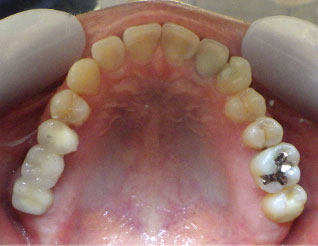

- ブリッジ 症例写真 B-0113FZC8本 女性モニターの方です。

この方は古い差し歯の黄ばみを治したいとご来院されました。 奥歯に欠損もありましたので、前歯はジルコニアセラミック、奥はジルコニアブリッジで治しました。 1回の治療で前歯も奥歯も同時進行で治療します。 1回目の治療時に仮歯を入れますので、すぐに見た目が気にならなくなります。 治療回数は5回でした。